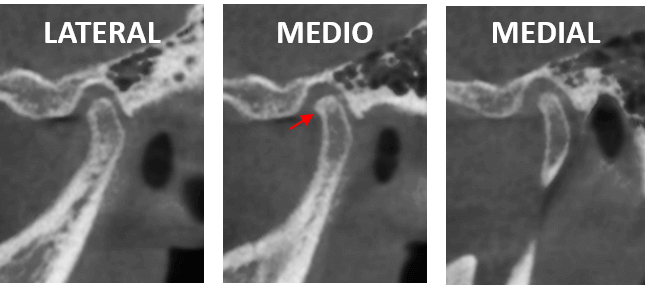

Fig.3

En los cortes sagitales de la ATM del lado izquierdo (Fig.3) se observa el aumento de la densidad ósea compatible con osteítis subcondral y la discreta formación de un osteofito a nivel de la vertiente anterior del cóndilo mandibular.